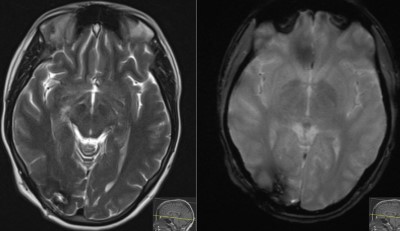

- Post-op